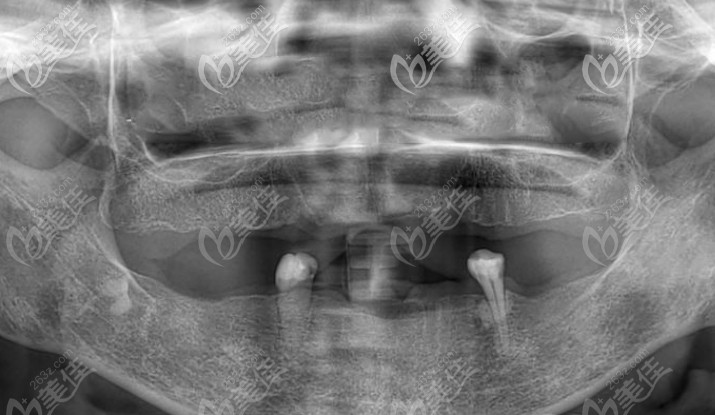

▲以上这是张奶奶拍的全景片,根本无法咀嚼食物

经过咨询医生才得知是由于长期缺牙导致牙槽骨吸收萎缩,通过一系列的拍片检查,建议张奶奶拔掉剩余无用牙齿,做满口bps吸附性义齿,来恢复她的咀嚼功能。